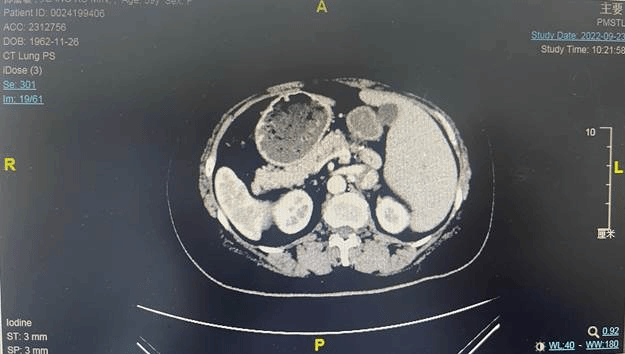

“按理说,人的肝脏都是长在右侧,女子的肝怎么在左侧出现了呢,检查时,我们就发现女子的身体不太正常?”ac米兰官网中文网站一院泌尿外科三病房副主任教授刘赞介绍。带着疑惑,医生们便为王女士进行仔细检查,这一查可不要紧,他们发现,王女士从腹部到胸部,所有的脏器全部“长反了”,也就是所谓的“镜面人”。

说到“镜面人”,修有成教授介绍,“镜面人”的发病率是百万分之一。“咱们全省是三千多万人口,那么也就是三十例左右吧,二十来人。如果不是这次发病,这名女性患者还不知道自己是个“镜面人”!通俗来讲,她胸腹中的所有脏器,全都长反了。”ac米兰官网中文网站一院泌尿外科三病房修有成教授介绍,鉴于患者解刨的特殊性,修有成教授、刘赞教授团队进行了周密的术前讨论和术前准备,最终决定用目前世界上最先进的达芬奇四代机器人手术辅助系统对病人进行微创手术

由于王女士的左肾上长出了一个恶性肿瘤,直径达到5厘米以上,体积已经超过了左肾的一大半。但是,由于王女士是“镜面人”,在术中也遇到了困难。

刘赞教授表示从医20年,他也是至今才遇到这么一例。“主要是解剖思维会受到影响。”刘赞教授介绍,正常人肝脏都是在右侧,她长在左侧了;脾脏,正常人在左侧,她长在右侧了;正常的胆囊应该在右侧,她长在左侧了。正常的左肾有脾遮挡,而如今对于左肾肿瘤有肝遮挡,我们只能事先考虑好,怎么通过这些遮挡,把肿瘤显露出来,让解剖更清晰。